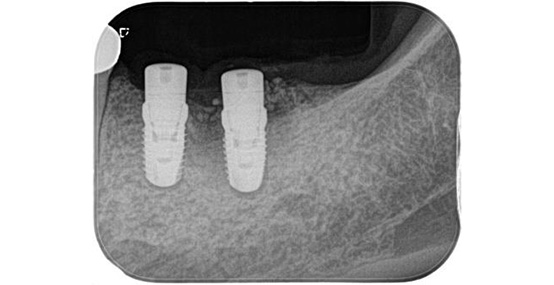

一次手術後のレントゲン写真です。

吸収していた骨の部分は人工の骨を足すことで無事に回復することができています。